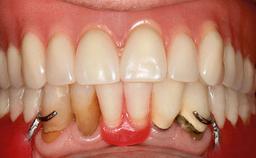

Surgical treatment of a 32-year old, healthy and non-smoking female who required removal and replacement of a lateral maxillary incisor due to internal root resorption. The inflammatory process caused a reduction of the crestal bone level on the distal side of the tooth necessitating an augmentation procedure to meet the patient's high esthetic demands. Due to the high smile line, the thin soft-tissue biotype and triangular-shaped teeth several esthetic risk factors are present.

Lip Line No exposure of papillae Exposure of papillae Full exposure of mucosa margin

Periodontal Phenotype Low-scalloped, thick Medium-scalloped, medium-thick High-scalloped, thin

Shape of Tooth Crowns Rectangular Triangular

Esthetic Risk High